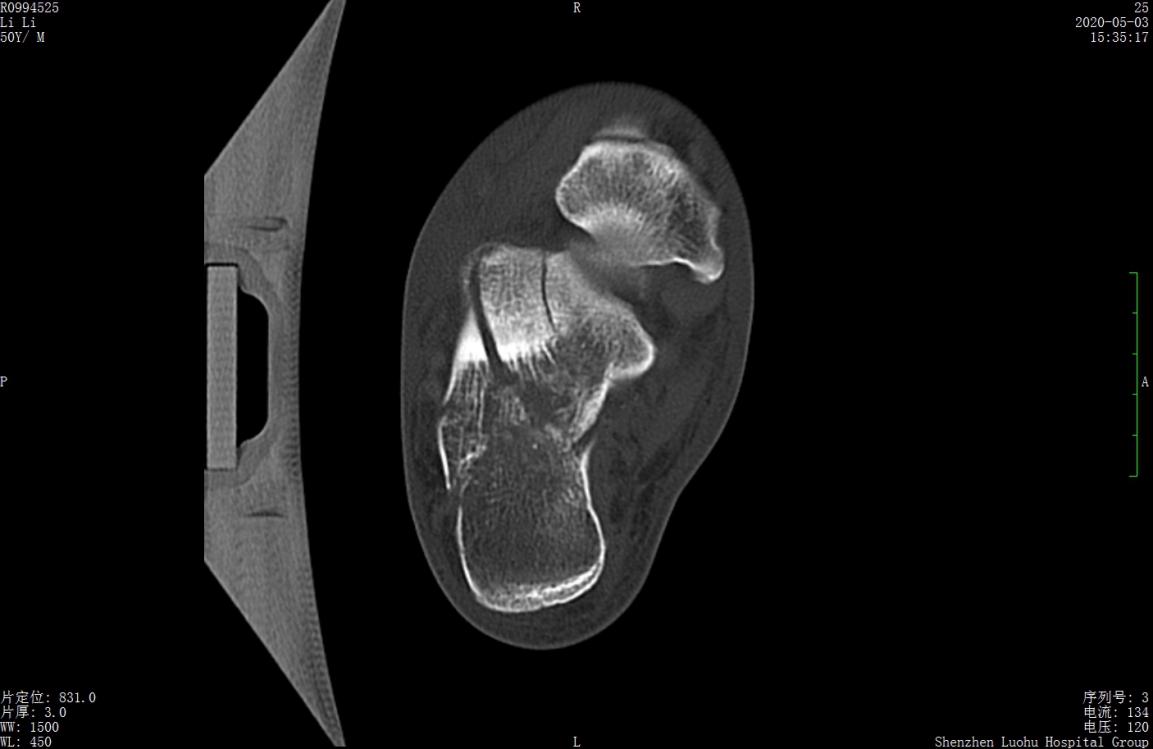

术前CT示跟骨严重粉碎骨折,移位明显

术前CT示跟骨粉碎骨折